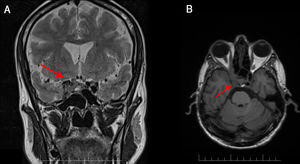

We present the case of a 49-year-old man with history of chronic obstructive pulmonary disease and category C3 HIV infection (CD4 count of 140 cells/mm3), diagnosed 3 months prior to admission. He was receiving regular treatment with bictegravir, emtricitabine, and tenofovir alafenamide. The patient reported right frontoparietal headache of 6 months’ progression, which led to several visits to the emergency department, where a head computed tomography (CT) scan was performed, revealing no alterations. He progressively developed diplopia and photophobia. The neurological examination revealed fluctuating ptosis, hyporeactive mydriatic pupil, and diplopia in all directions of gaze, with limited infralevoversion, levoversion, and supraversion, all involving the right eye. No meningeal signs or fever were observed. A brain MRI study revealed a contrast-enhancing mass in the right cavernous sinus, extending to the orbital apex and affecting the wall of the right internal carotid artery (Fig. 1). A routine biochemical analysis and blood count detected no relevant abnormalities. Cerebrospinal fluid (CSF) analysis revealed no red blood cells, 3 nucleated cells, lactate level of 8.8 mmol/L, protein level of 0.37 g/L, and glucose level of 0.47 g/L; adenosine deaminase levels were normal. A chest, abdomen, and pelvis CT scan revealed no pathological findings. Serology for toxoplasma, syphilis, and Borrelia, and a PCR test for cytomegalovirus yielded negative results. Gram staining and CSF culture for bacteria and mycobacteria also returned negative results. Testing for the galactomannan antigen and (1-3)-β-d-glucan and PCR test for Aspergillus yielded negative results in serum and CSF. PCR testing did not detect Pneumocystis jirovecci, Cryptococcus neoformans, or Histoplasma capsulatum in the CSF. A biopsy specimen of the lesion was obtained through the endoscopic endonasal transsphenoidal approach. Gram staining, cultures, and PCR testing of the specimen yielded negative results for fungi and bacteria. A histological analysis revealed an inflammatory lesion with abundant histiocytes, neutrophils, and fungal colonies suggestive of Aspergillus spp. Based on the anatomical pathology results, we collected a sample to repeat the PCR test, which finally yielded positive results for Aspergillus spp. We administered a 2-week course of intravenous antifungal treatment with voriconazole at 6 mg/kg every 12 hours during the first day, followed by 4 mg/kg every 12 hours and liposomal amphotericin B at 4 mg/kg every 24 hours. Amphotericin was switched for intravenous caspofungin at 50 mg/kg due to impaired renal function and hyponatraemia. Voriconazole was suspended after 10 days due to hepatotoxicity, and we started oral posaconazole at 300 mg daily at discharge. Antiretroviral therapy was not modified. At a 5-month follow-up visit, we observed good clinical progression, with the patient being asymptomatic. From a radiological viewpoint, the patient was stable, with the follow-up MRI scan showing no changes.

Aspergillus fumigatus is the most frequent cause of aspergillosis in humans. Although it mainly affects immunocompromised patients, its incidence is low in patients with HIV, and is usually limited to those with a CD4 cell count below 100 cells/mm3. In 80% of cases of invasive aspergillosis in patients with HIV infection, the lesion is located in the lungs; involvement of the cavernous sinus is rarely reported.7–9 Brain MRI is the most useful tool for diagnosing the condition, although a definitive diagnosis is not always reached.1,10 Cavernous sinus involvement is typically characterised by heterogeneous, hypointense lesions on T1- and T2-weighted sequences, as well as a tendency to invade nearby vessels, as in our case, in which we observed involvement of the internal carotid artery (Fig. 2).11–13 Laboratory tests are usually inconclusive.14 Testing for galactomannan antigen and (1-3)-β-d-glucan in the serum and PCR testing for Aspergillus are useful tools, although sensitivity may be affected in cases with sinus involvement.9 In our case, the first PCR test of the biopsy specimen yielded negative results; therefore, obtaining a specimen for histological analysis was essential for management and definitive diagnosis. However, collection of the specimen was limited by the patient’s clinical status and the delicate anatomical location.